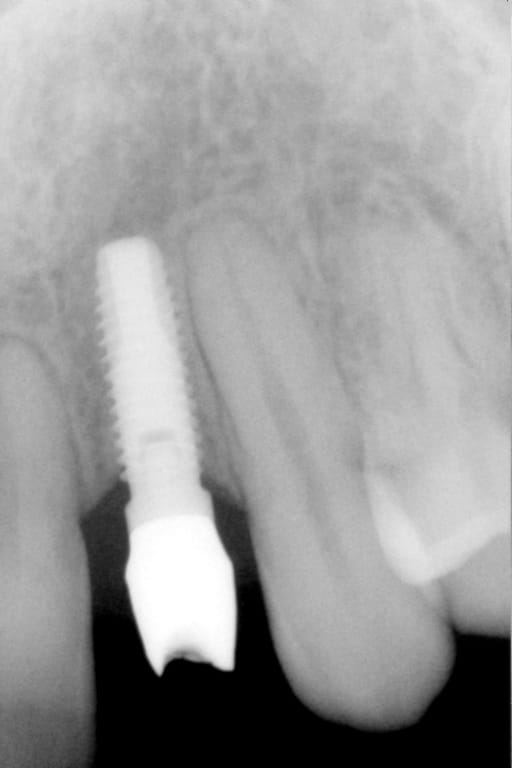

On m'a dit que Pluton était incollable sur les implants.

Alors, j'aimerais demander à Pluton s'il sait ce que c'est...

dis m'en un peu plus sur ce cas car c'est un implant avec un hexagone externe et j'ai beaucoup de correspondances....

cela dit, hex externe en général c'est une plateforme standard et quasi toutes les marques sont compatibles

donc çà limite un peu les recherches sur les marques disponibles en france à cette époque et la marque d'implant qui match le plus avec les caractéristiques que tu m'as montré (hex externe, apex plat, spires en V, col large, vis de cicat avec hexagone....) c'est un implant Biomet 3i osseotite parallel walled